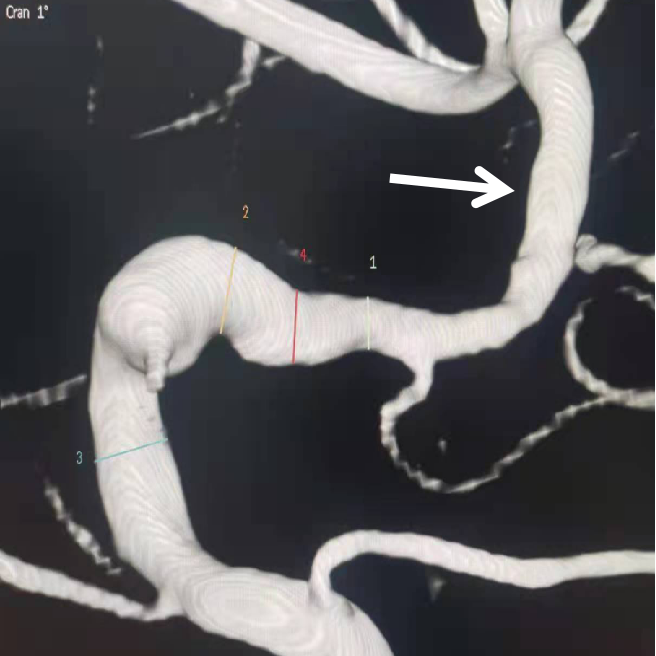

左侧颈内动脉末端梭形夹层动脉瘤,2.9mm*3.5mm。

Marksman™ 导管0.014" 200cm 微导丝Pipeline™ Flex血流导向密网支架 PED-325-25